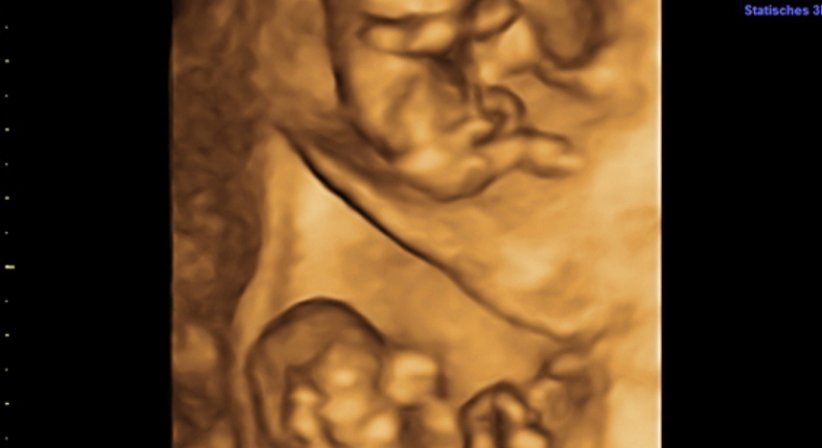

Zwillinge, Drillinge und höhergradige Mehrlinge sind natürlich immer ein großes Erlebnis für Eltern, deren Familie und Freunde, aber auch für den Geburtshelfer.

Entscheidende Bedeutung für den Verlauf einer Mehrlingsschwangerschaft ist die Ultraschalluntersuchung zwischen SSW 8 und 12. Dabei wird nämlich festgestellt, ob sich die Kinder einen Mutterkuchen teilen müssen oder jedes einen eigenen zur Verfügung hat. Dieser Unterschied ist sehr wichtig für die weitere Führung der Schwangerschaft.